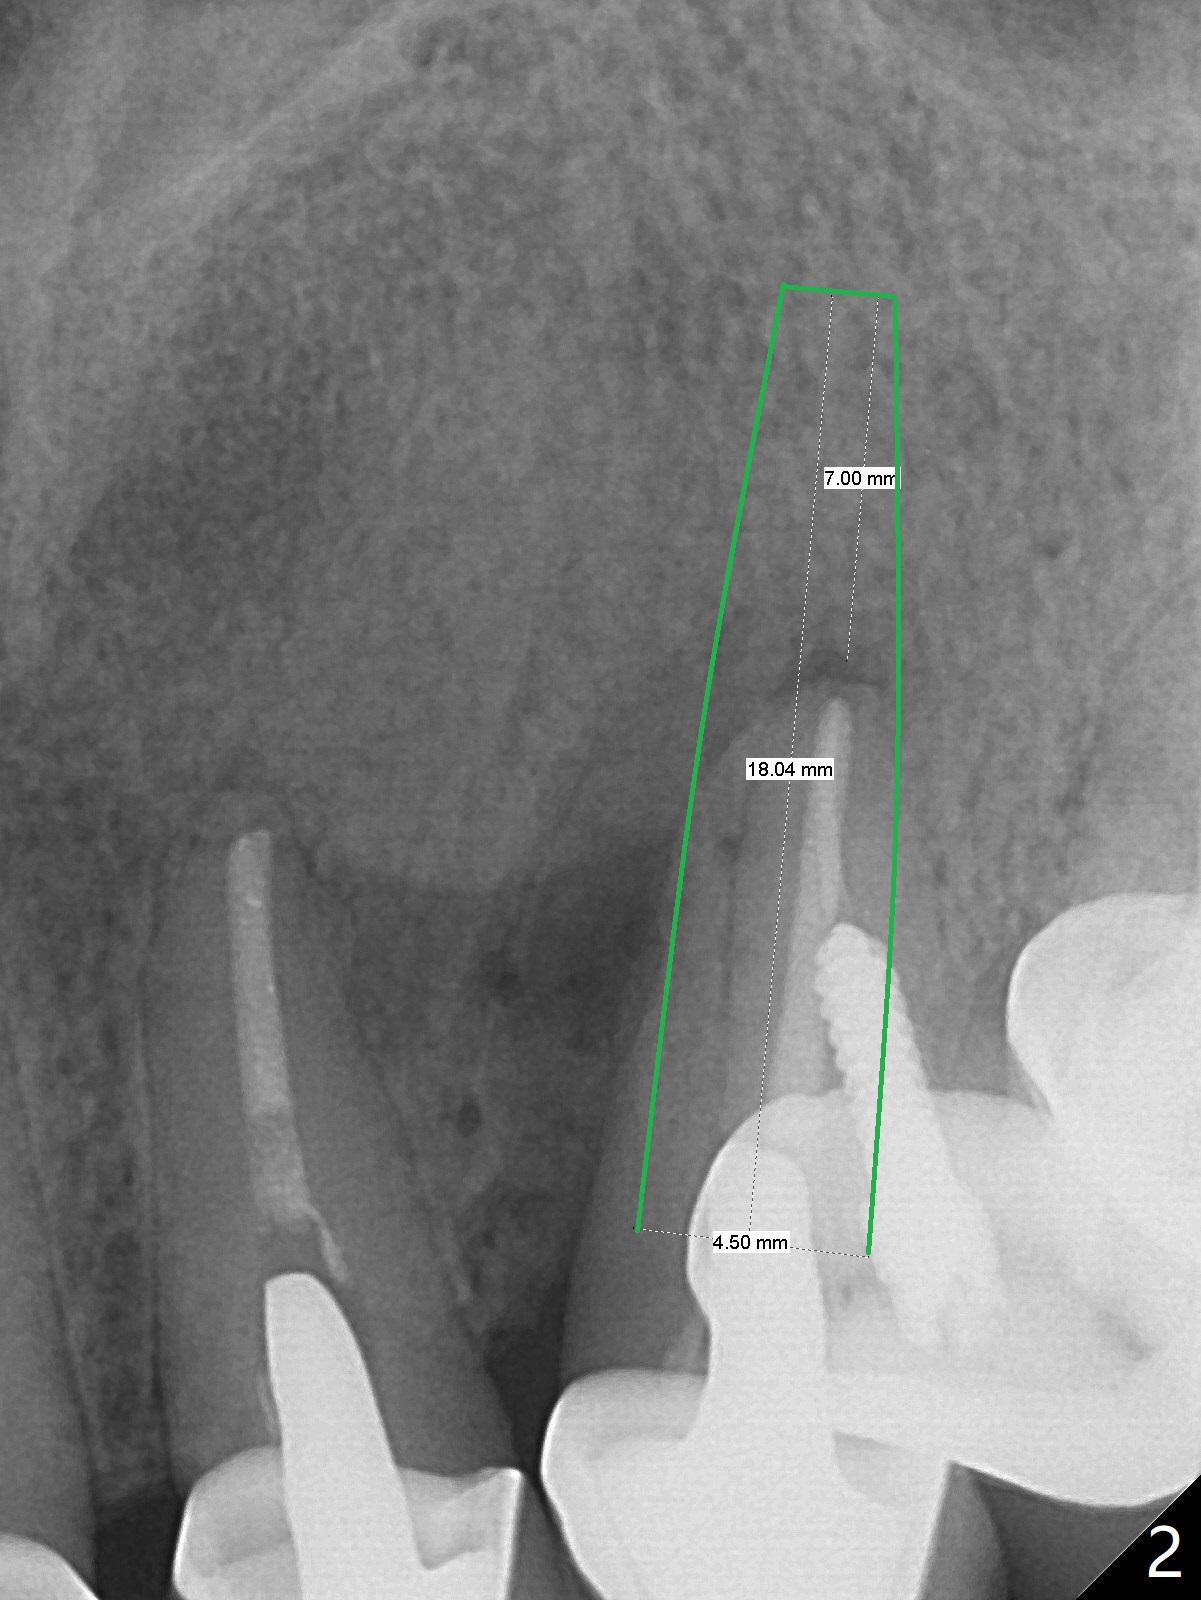

A 52-year-old woman has possible vertical root fracture at #11 (Fig.1 arrowheads (mesial radiolucency: *)) associated with several missing molars. For primary stability, the longest bone-level implant will be placed (Fig.2) with 7 mm in the native bone.